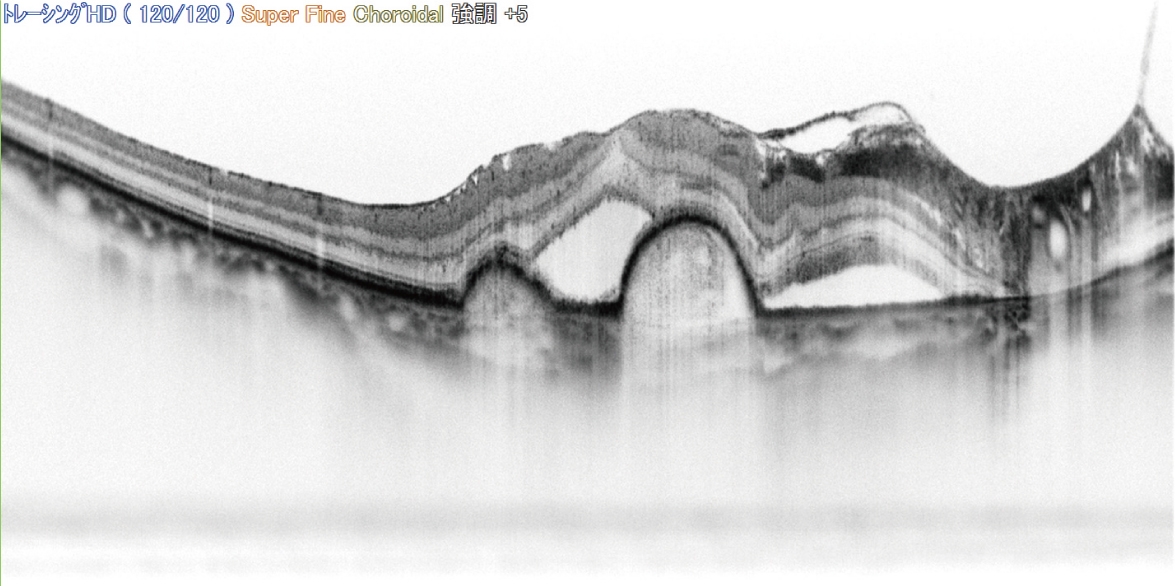

SLO イメージ & トレーシング HD plus